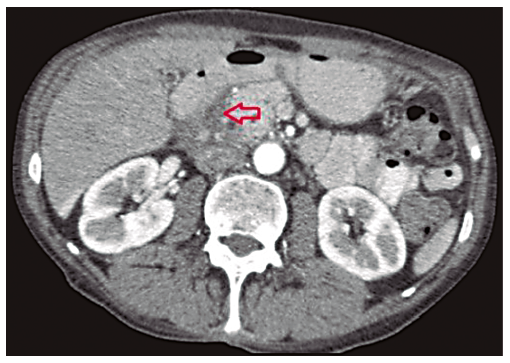

En la TCMD de abdomen con contraste endovenoso se observan imágenes quísticas parietales (Figura 2) y engrosamiento de la pared duodenal con estrechamiento de su luz (Figura 3). Además se logra visualizar a nivel del surco pancreaticoduodenal rarefacción de la grasa y dilatación del colédoco (Figuras 4 y 5).

Afecta predominantemente a varones entre 40 y 50 años con historia de abuso de alcohol, aunque su etiología es incierta.3 El diagnóstico representa un desafío para el médico radiólogo, que frente a una masa de morfología laminar entre la cabeza pancreática y la segunda porción duodenal, que se presenta en la TCMD como una formación hipodensa (Figura 4) acompañada de engrosamiento concéntrico de la pared duodenal con estenosis de su luz,4 y presencia de formaciones quísticas en la pared del mismo.5 (Figuras 2 y 3), debe reconocer los múltiples diagnósticos diferenciales, como el carcinoma ductal pancreático y el carcinoma duodenal.